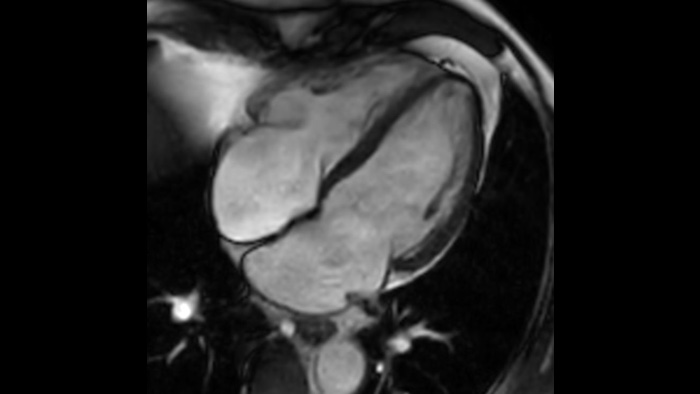

Diagnostic confidence Expand your imaging capabilities in all clinical areas. See how your peers are benefiting.

The Ingenia Ambition 1.5 Tesla magnet is the next generation of MR technology. It brings together the most important aspects of having a successful MR system.

Speed & Comfort Provide up to 40% reduction in breath holds, with virtually equal image quality4.

Learn how MCVI boosts MRI quality.